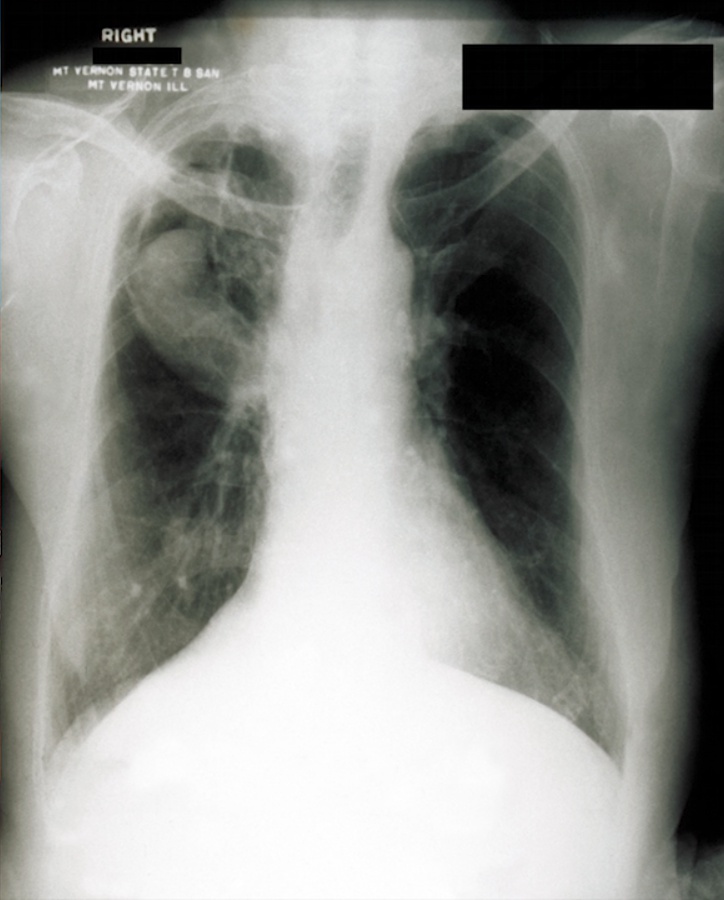

Hilar calcifications: on Xray

coughing: pneumonia

lung wall holes, bricks caved in/out: Radiographic images may show either nothing or cavities and/or nodules.